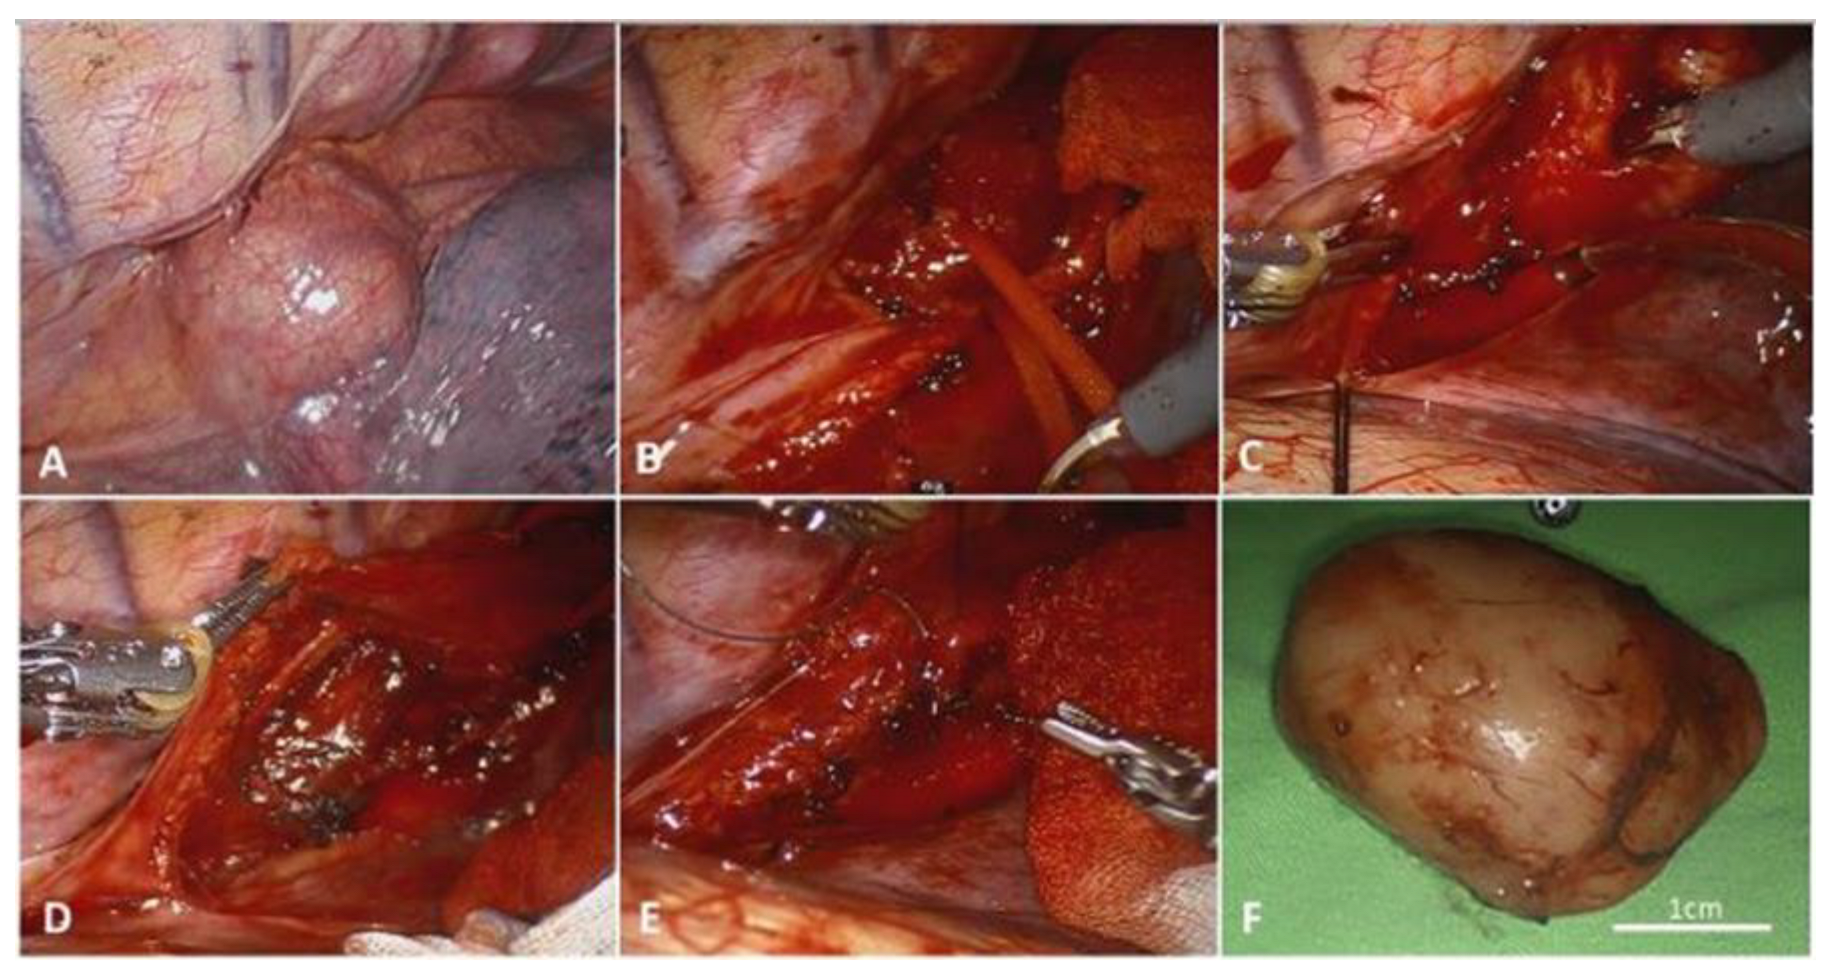

| 4 | 86/M | Lt ★ | 22 | Dysphagia | Lipoma | 151 | 12 |

| 7 | 34/M | Lt ★ | 12 | Dysphagia | GIST ◆ | 247 * | 19 |

| 16 | 67/M | Lt ★ | 10 | Dysphagia | GIST ◆ | 241 * | 53 |